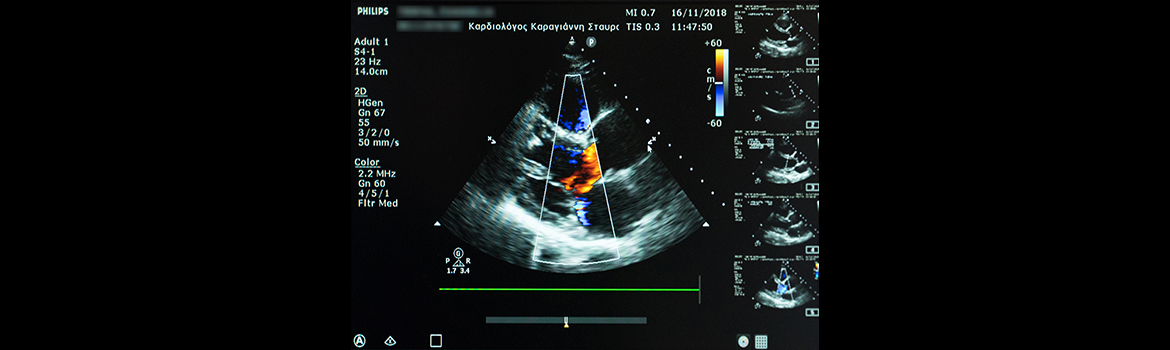

Με το triplex καρδιάς και μεγάλων αγγείων μπορούμε να εκτιμήσουμε το μέγεθος της καρδιάς, την δύναμη συστολής της (κλάσμα εξώθησης), την λειτουργικότητα των βαλβίδων αποκλείοντας στένωση ή ανεπάρκεια αυτών, να ανιχνεύσουμε τη συλλογή περικαρδιακού υγρού, να διαγνώσουμε την ύπαρξη ανευρύσματος της αορτής, να αποκλείσουμε σοβαρές μυοκαρδιοπάθειες (διατατική ή υπερτροφική) κ.λ.π.